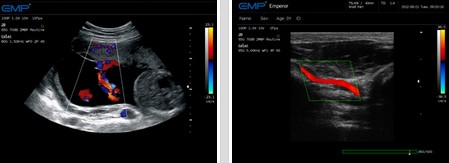

● 方向能量图(PDI) ——血流成像更简便敏感,是检测血管疾病的有效手段

● 彩色多普勒(CFM) ——实时无创显示区域血流信息,检测客观精确

● 敏感的血流测量 ——优秀的超低速血流检测技术,精度高,用时短

● 优秀的3D成像 ——以更加生动形象的方式提供更多临床重要的信息

临床图像